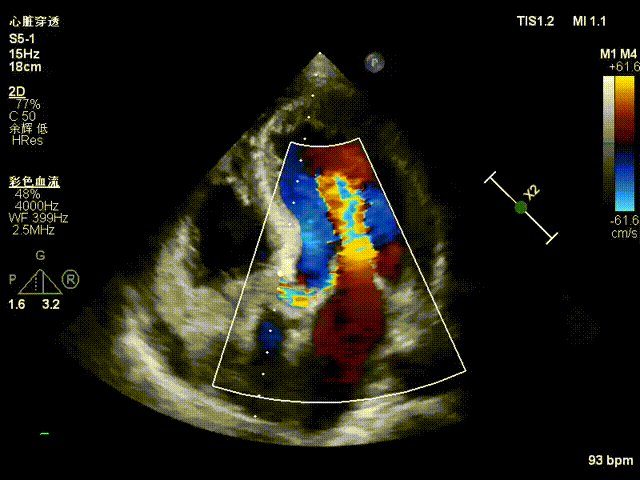

TTE入院

TTE